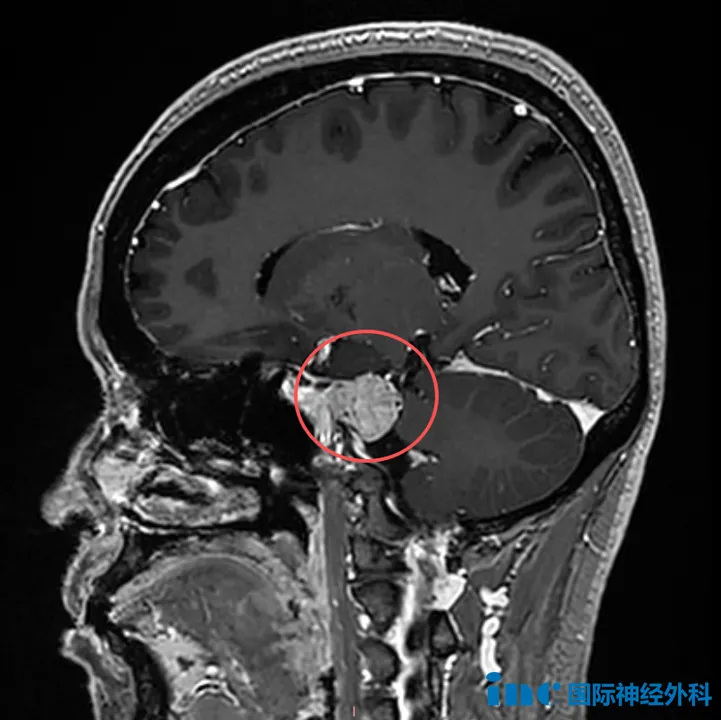

如果要问我哪种手术最让人心里没底,岩斜区脑膜瘤绝对排得上...

头痛、视力下降、眼球不能正常转动……不少患者拿到颅底肿瘤...